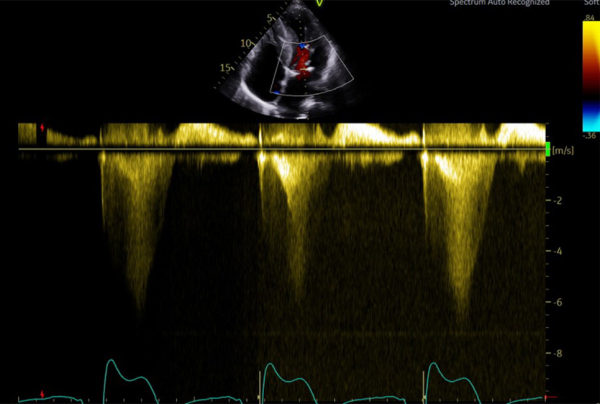

Figure 2 : flux Doppler continu trans-aortique d’obstruction

Figure 3 : flux Doppler continu trans-mitrale d’IM

Figure 4 : superposition des 2 flux Doppler continu d’obstruction sous aortique et d’IM

- Patient de 40 ans avec une CMH sarcomérique (mutation HTZ MYBPC3) avec épaisseur maximale en antéro-septo-basal à 33mm en IRM, associée à une obstruction sous aortique significative (GD max 77 mm Hg au Valsalva). Découverte d’une insuffisance mitrale (IM) sévère mixte organique sur prolapsus de P2 et fonctionnelle sur un SAM (mouvement systolique antérieur de la valve mitrale)

Figure 5 : flux Doppler continu trans-aortique

Il s’agissait d’une hémolyse mécanique en lien avec l’obstruction sous aortique (Gradient max 68 mm Hg) favorisée par un SAM de la valve mitrale à l’origine de la persistance d’une IM de haut grade. On suspectait notamment un SAM de néo cordage. Un contact direct entre hématies et anneau prothétique à l’origine d’un stress mécanique est possible aussi mais plus anecdotique.

Le septum inter ventriculaire est mesuré à 18mm contre 21 mm avant initiation du traitement et le gradient max en doppler continu trans-aortique au Valsalva a diminué de 68 mm Hg à 45 mm Hg.

Figure 6 : flux Doppler continu trans-aortique